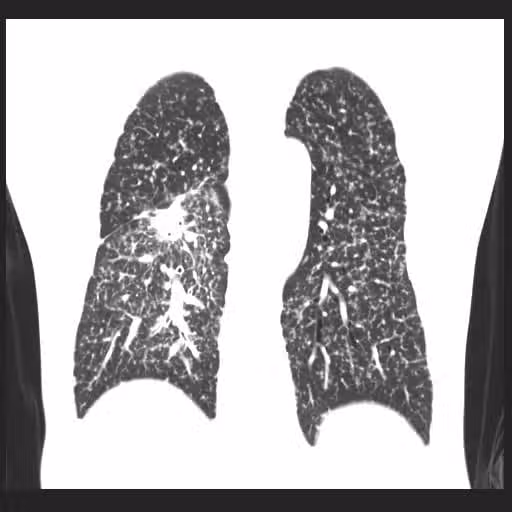

全家都罹癌!他小咳一個月檢查「竟是肺癌末期」 醫嘆「用錯電器、清潔劑」等於抽20支菸

圖片來源:蘇一峰臉書

蘇一峰表示,該病人平常熱愛運動、跑馬拉松,而且不菸不酒,從外表看來精神飽滿、體力很好,但其實,台灣有六成的肺癌患者,本身都沒有抽菸習慣,更該受到重視的,其實是二手菸、煮菜油煙、馬路空汙等危險因子,如果排除上述因素,就有可能和「家族遺傳」有關…不少病人都是家人確診後,連帶著也檢查發現。